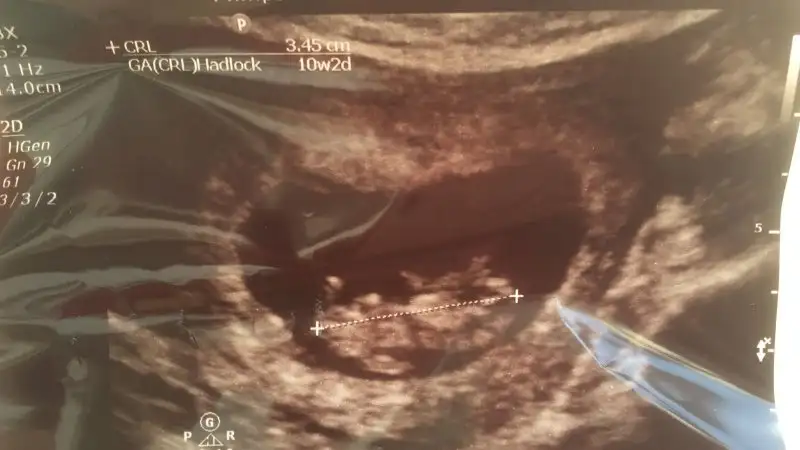

Ben yorum yaptım şimdi sıra bende ben zaten hissediyordum en baştan erkek doyordum yumurtlama günü ilişki olmuştu çünkü şimdi kız dese sasiririm yani .

Ben erkeğim diyor resmen

• 20180529_123757.webp

12,5 KB · Görüntüleme: 312